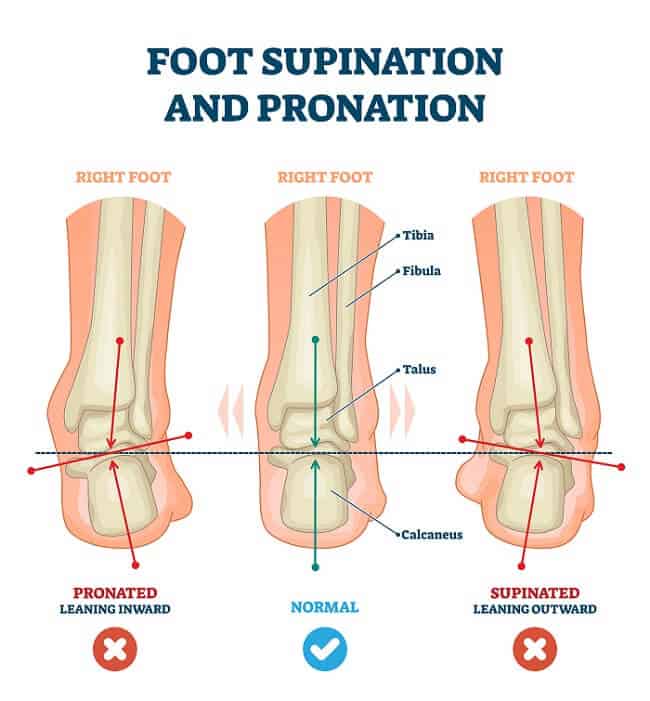

Foot Postures: What It Means for Your Feet?

Flat Feet (Fallen arches) – Pronation & Supination of your feet …

Pioneer Podiatry – Flat Feet, Collapsing Arches, Over-Pronation & High …

Flat Feet Overpronation Causes, Treatment and Prevention | OrthoFeet